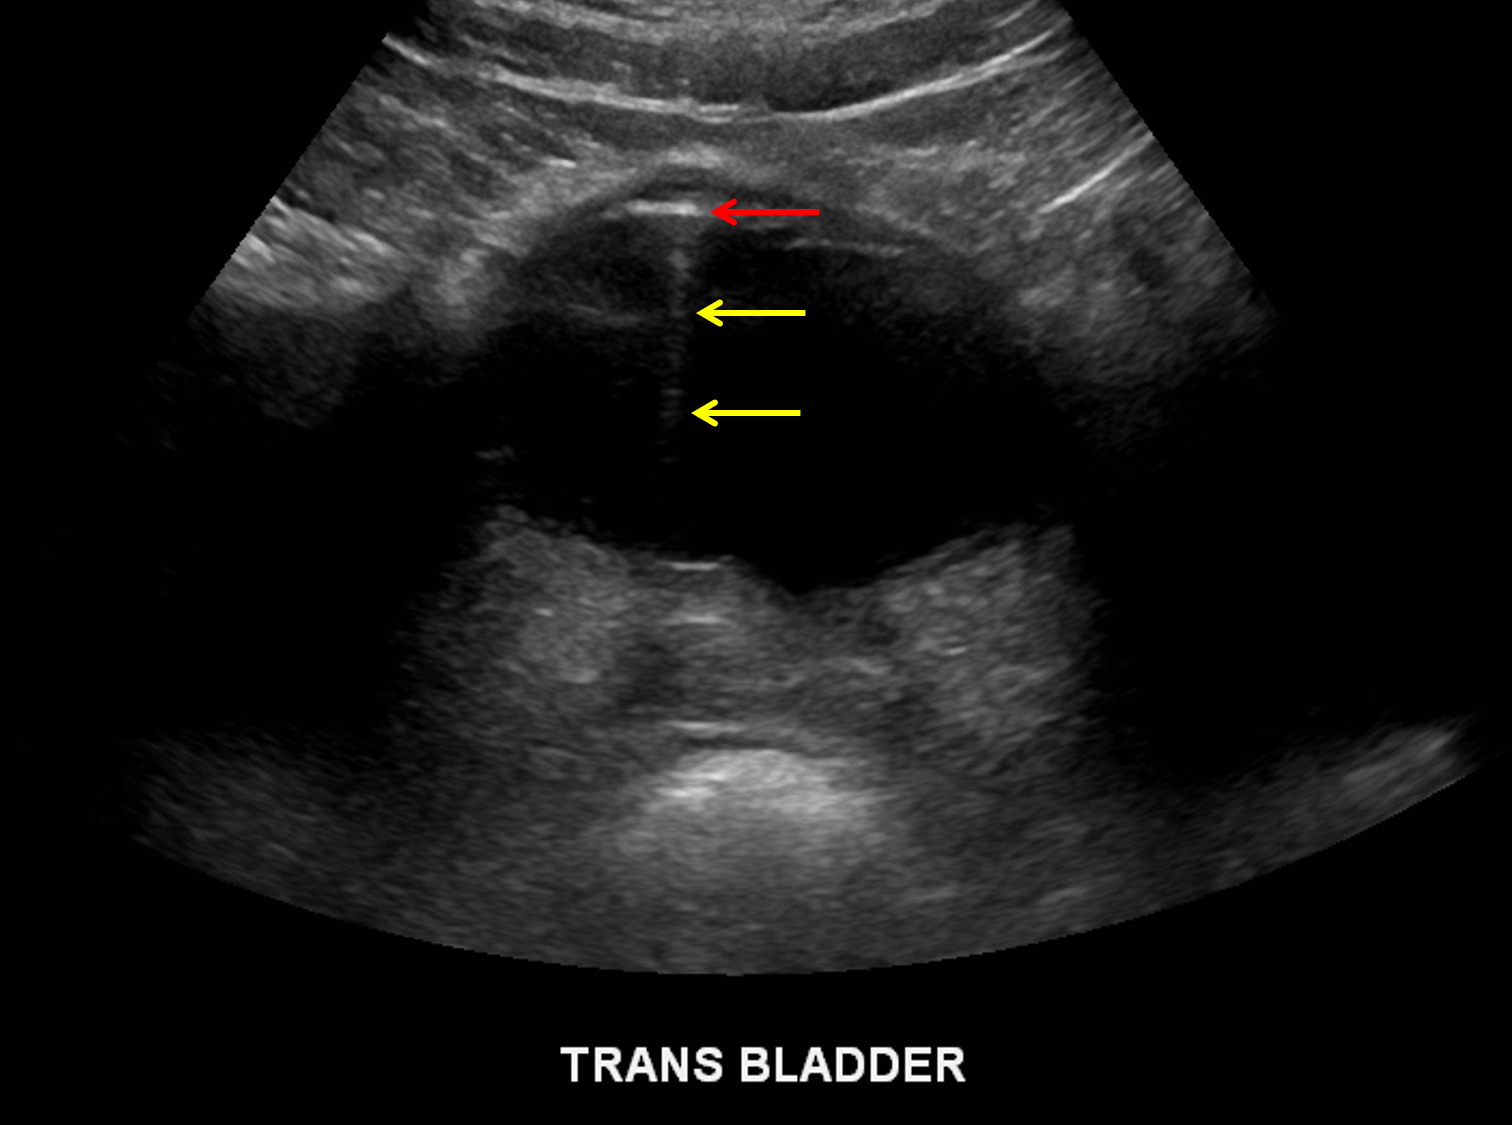

Ultrasound